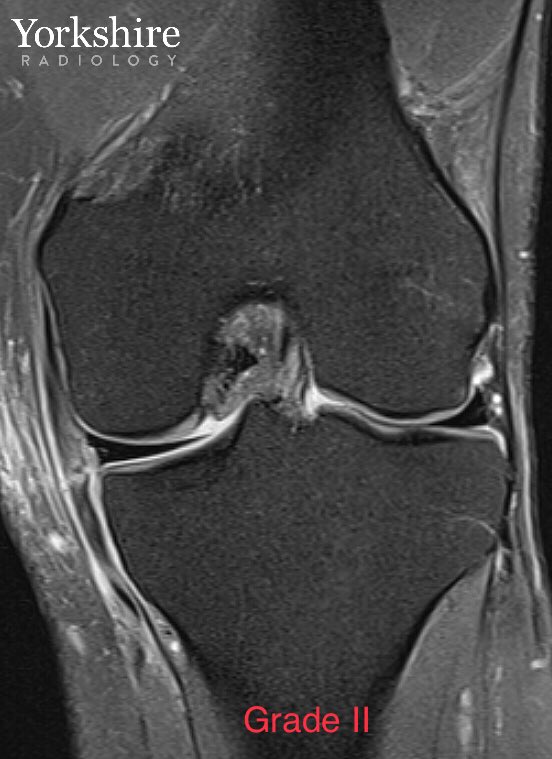

MCL injury gallery. Grade 1, 2 & 3. #orthotwitter